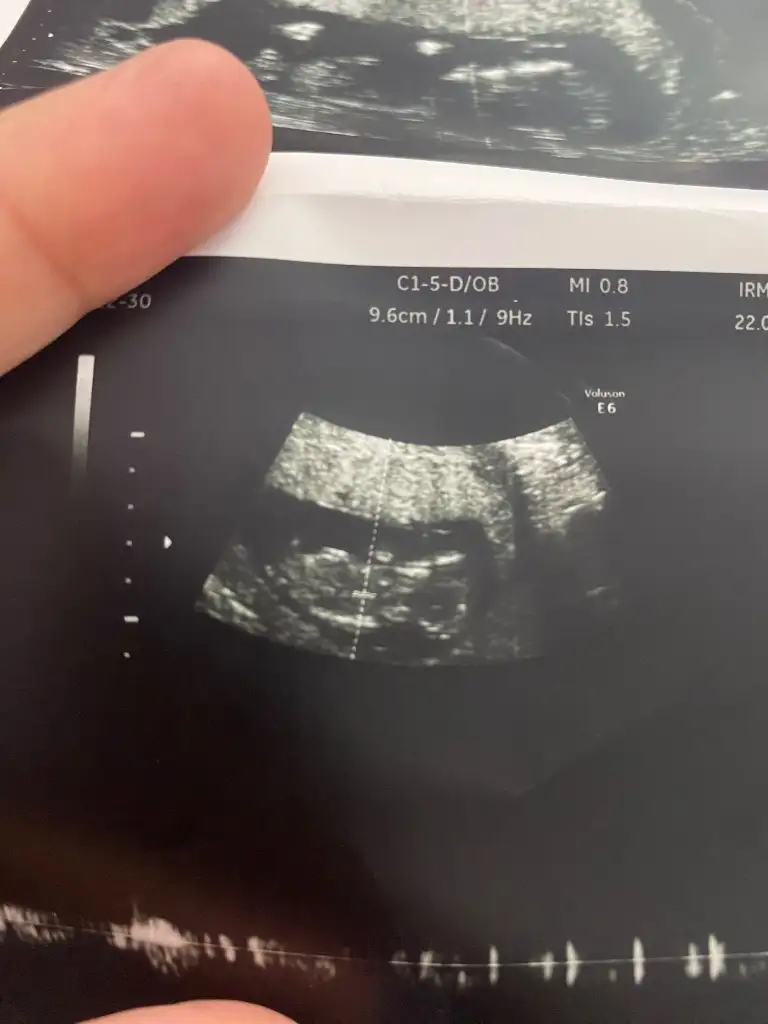

13. Haftaya yeni girdik tahmininiz nedir acaba?

• c45671b1-548e-44e6-85d4-cf0b1aea9f9f.webp

c45671b1-548e-44e6-85d4-cf0b1aea9f9f.webp

19 KB · Görüntüleme: 238